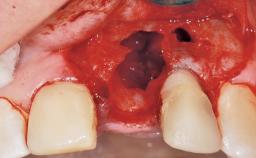

Immediate Placement of an Implant in a Maxillary Right Central Incisor Site

A 30-year-old female patient was referred to the office for the treatment of tooth 11. Her chief concern at the initial visit was to inquire, “Why is my tooth pink?” Upon clinical examination, it was determined that tooth 11 had a previous history of trauma and that the clinical crown had become noticeably pink in color as a result of internal resorption. This diagnosis was confirmed radiographically, indicating a large radiolucency involving the central and distal portions of the clinical crown. It was determined that restoration of this tooth was not possible, and that extraction was indicated. The presence of a mid-line diastema, which the patient wanted to reproduce, directed the treatment plan for tooth replacement utilizing a dental implant.

Bone Augmentation Horizontal|Simultaneous

Augmentation Materials Autogenous chips|Membrane

Placement Protocol Immediate implant placement

Socket Integrity Sufficient, with intact bone walls

Bone Volume Sufficient, with intact walls